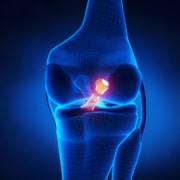

The fingers are made up of bones called phalanges. The phalanges in each joint are separated by two joints called interphalangeal joints (IP joint). The two joints are the distal IP joint (DIP joint), meaning further away, and the proximal IP joint (PIP joint), meaning the middle or closer in. These IP joints of the fingers are like hinge joints, allowing us to have mobility with our hands, including straightening and bending.

Swan neck is a deformity, in simple terms, a crooked finger. The PIP joint (the joint in the middle of the main knuckle and DIP joint), includes the strongest ligament called the volar plate. These ligaments connect on the palm side of the joint. As the ligament tightens when the finger is straight, the PIP joint is protected from bending back too far, or hyperextending. Swan neck deformity occurs when the PIP joint in the finger becomes hyperextended and the DIP joint at the end of the finger is flexed, causing a crooked finger.